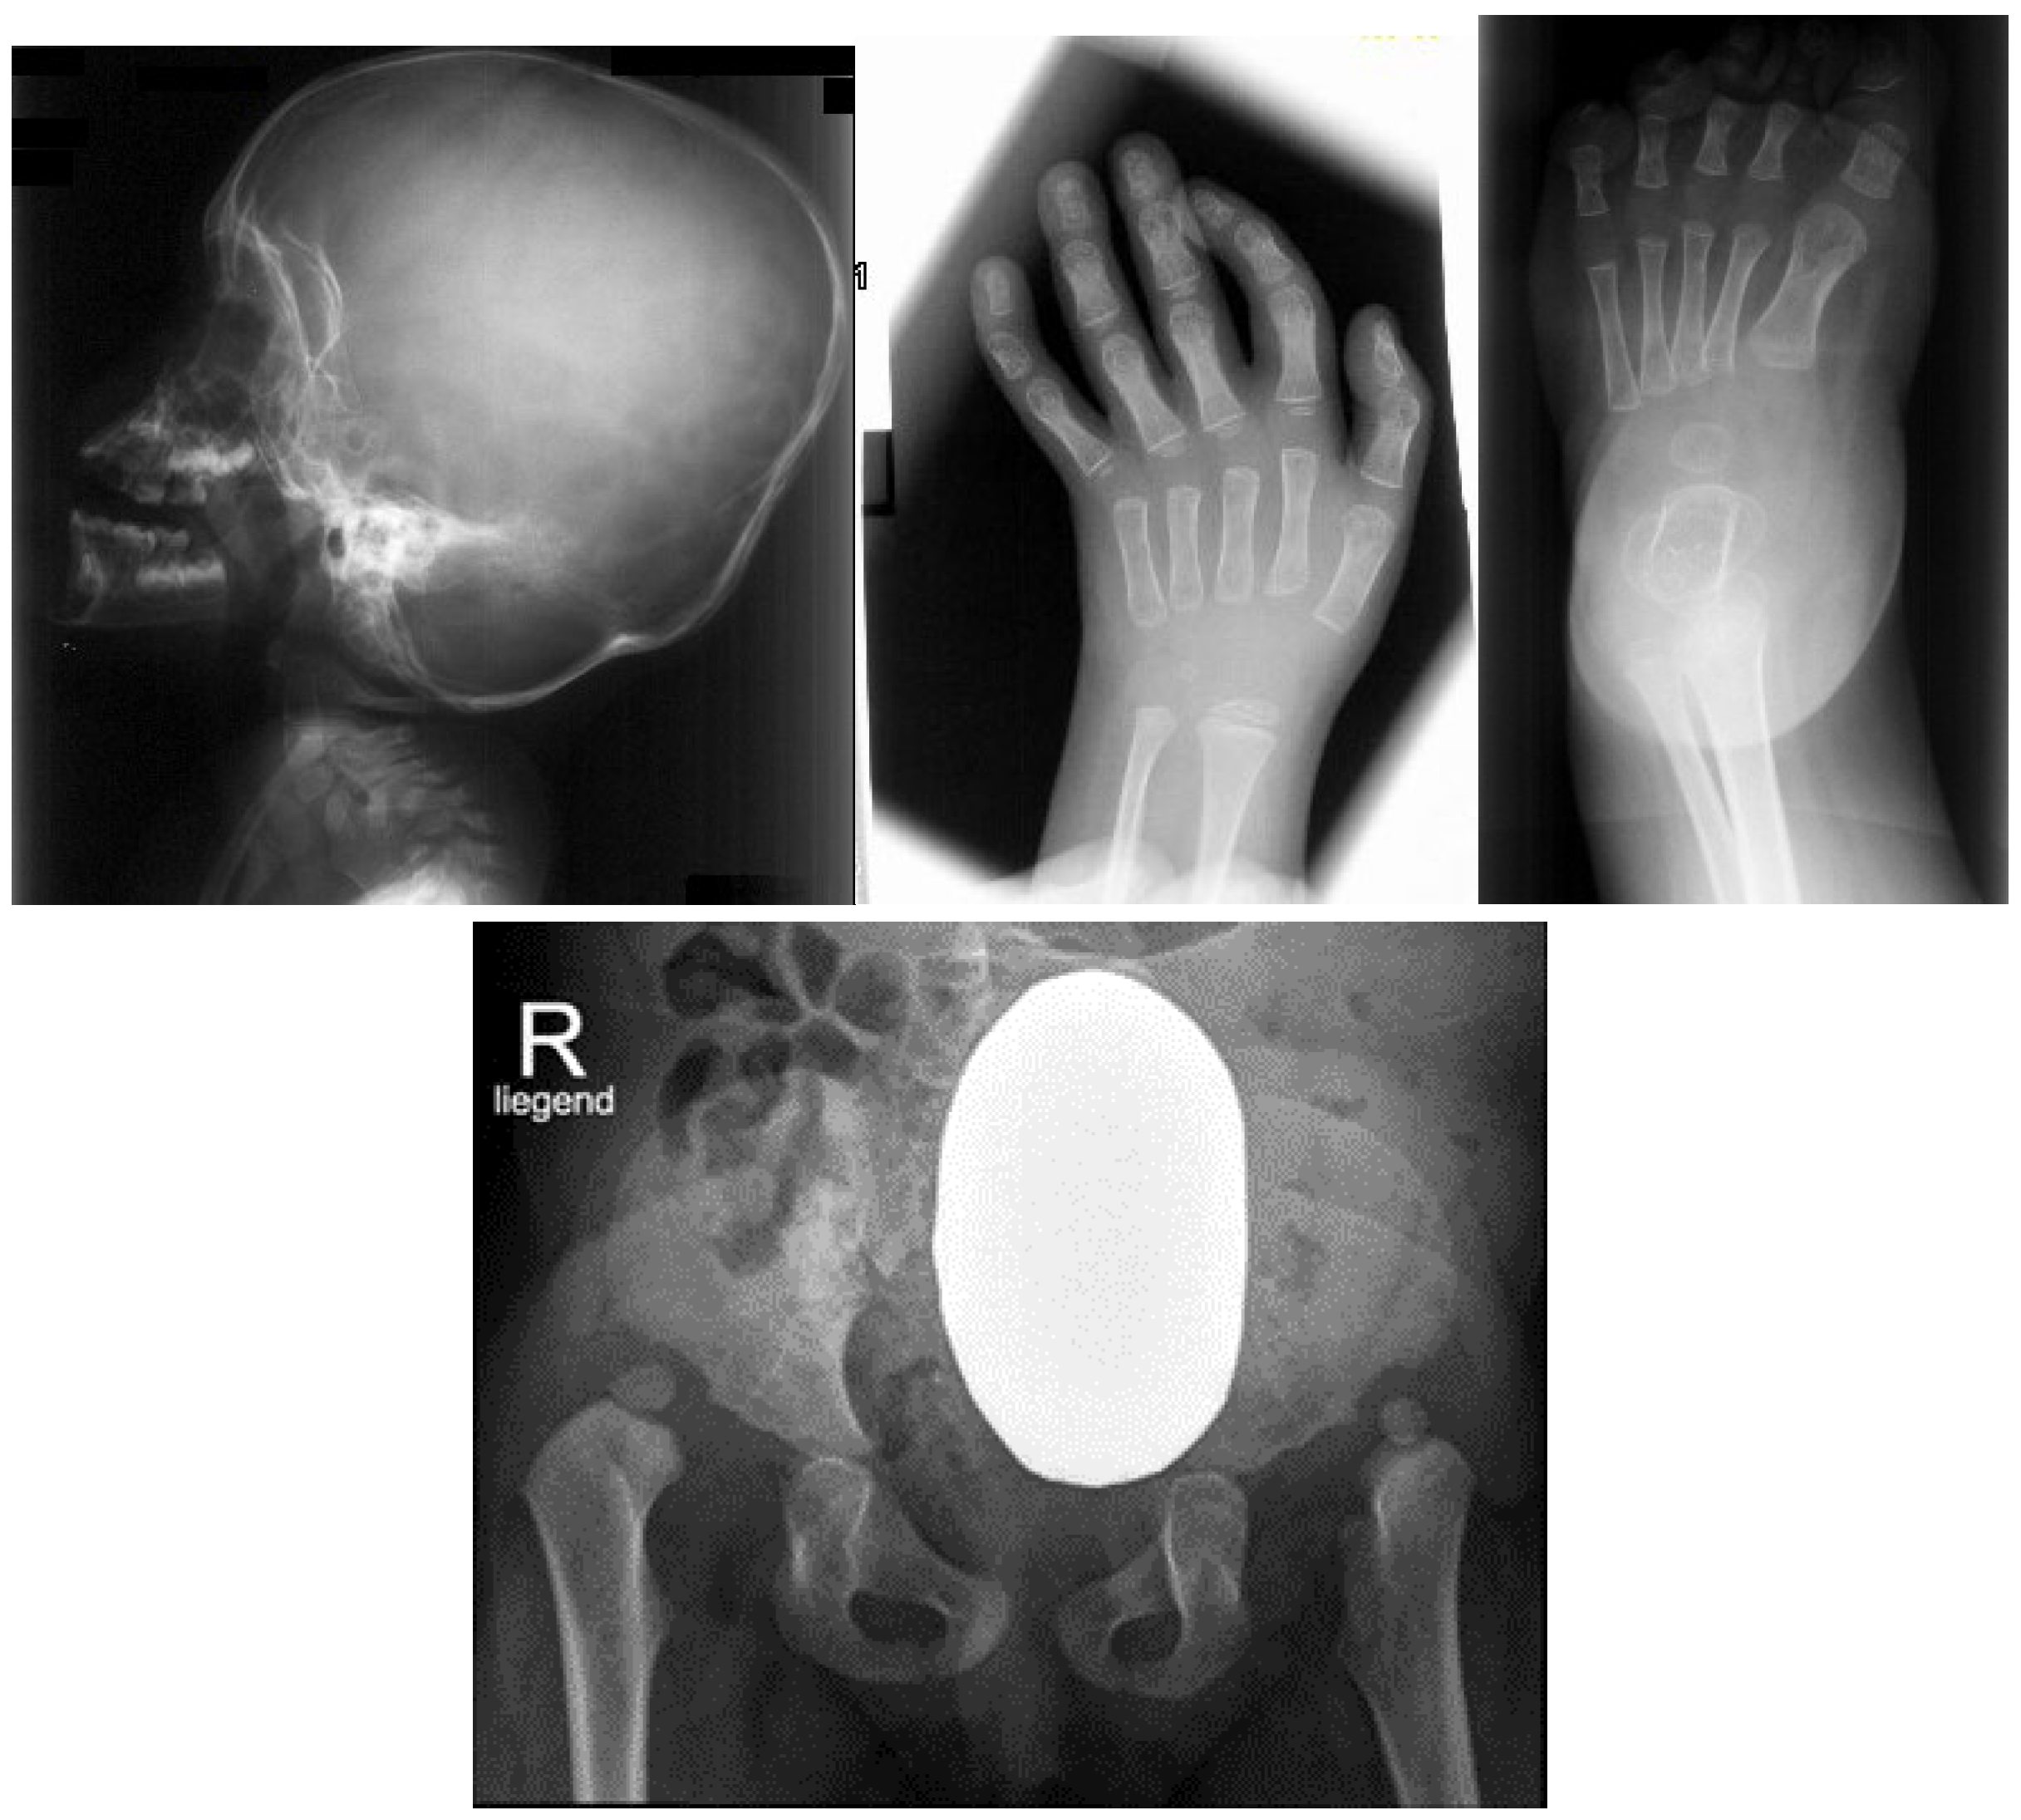

3.1. The Classical Clinical and Radiological Phenotype in Children with Larsen Syndrome